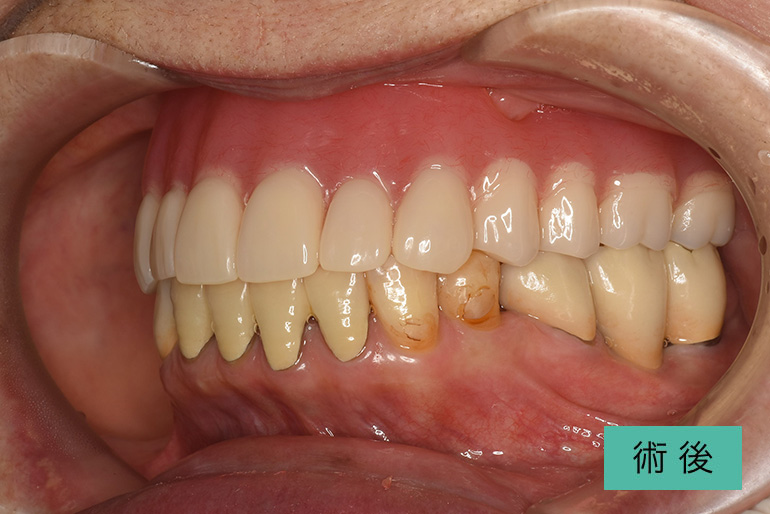

インビザライン③

| 治療内容 | 歯並びをキレイにしたい。 口腔内容積を狭くしないように、歯列を拡大し非抜歯で矯正をする。 |

|---|---|

| 治療期間・回数 | 約6年、80回 |

| 費用(税込) | ¥880,000(マウスピース矯正) ¥620,000(セラミッククラウン) ※自由診療 |

| リスク・副作用 | 歯肉退縮、知覚過敏、後戻り |